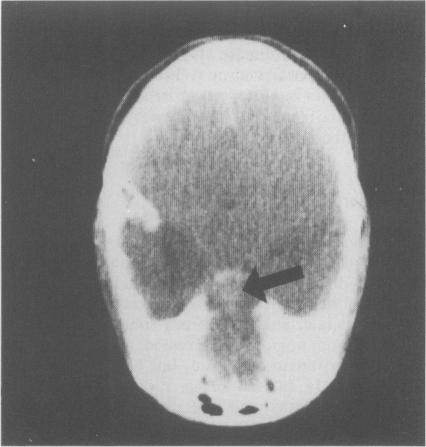

A 32 year old female with hyperprolactinaemia-galactorrhoea-amenorrhoea due to a right internal carotid artery aneurysm just before its bifurcation is described. She had two episodes of subarachnoid haemorrhage necessitating an emergency internal carotid artery ligation. She responded to bromocriptine treatment with restoration of her menses, normalization of circulating prolactin and disappearance of galactorrhoea.

本文描述了一名32岁女性,因右侧颈内动脉动脉瘤(恰好在其分叉前)导致高泌乳素血症 - 溢乳 - 闭经。她曾发生过两次蛛网膜下腔出血,需要紧急进行颈内动脉结扎术。她对溴隐亭治疗有反应,月经恢复,循环泌乳素水平正常,溢乳消失。